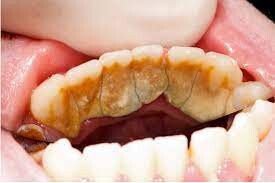

When plaque builds up in your mouth, it can turn into an even greater dental health threat: calculus. This formation, also known as tartar, is a calcified mass that adheres to your teeth. Calculus is classified as either supragingival or subgingival, depending on its location on your teeth. If left unremoved, subgingival calculus can lead to gum disease and tooth loss.

An article published in the International Journal of Dental and Health Sciences (IJDHS) explains that plaque, which is a sticky film of bacteria that constantly forms on your teeth, can mineralize due to the exchange of calcium and phosphate ions present in your saliva. This process is what creates calculus, a hard mass of bacteria stuck to your tooth surfaces.

Plaque can harden into calculus in as little as four to eight hours. The average length of time for mineralization, however, is 10 to 12 days. Calcification times can vary from person to person, depending on their salivary pH and the amount of calcium and other substances in their saliva. Once calculus forms, it then attracts more plaque, which in time can become another layer of calcified material.

Characteristics of Subgingival Calculus

Tartar that accumulates on your teeth above the gumline and is easily seen by your dentist or dental hygienist is called supragingival calculus, according to the IJDHS article. But the tartar that forms below the gumline — and is therefore not immediately visible — is known as subgingival calculus. This type of calculus is usually dark brown to greenish black in color and can be detected with a dental instrument called an explorer.

It's important to note that, while you can clean plaque off your teeth with brushing and flossing, hard tartar can only be removed by a professional cleaning, explains the American Academy of Periodontology (AAP). Your dentist or dental hygienist uses special instruments that are designed to remove the calculus.